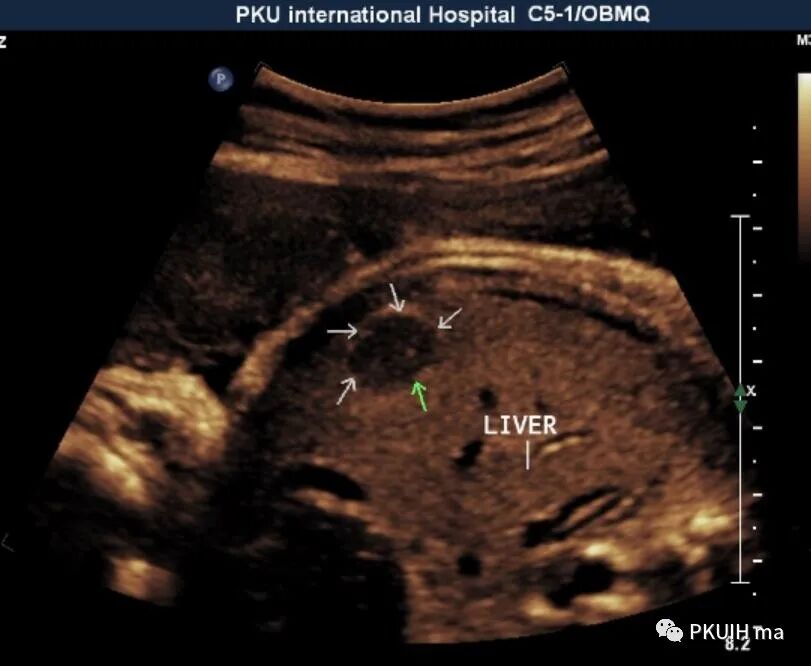

胎儿右肝内见一大小约1.4cm的实性低回声结节,边界清,形态规则,内回声均匀

CDFI内血流不明显,用CDE发现结节内见少许血流信号